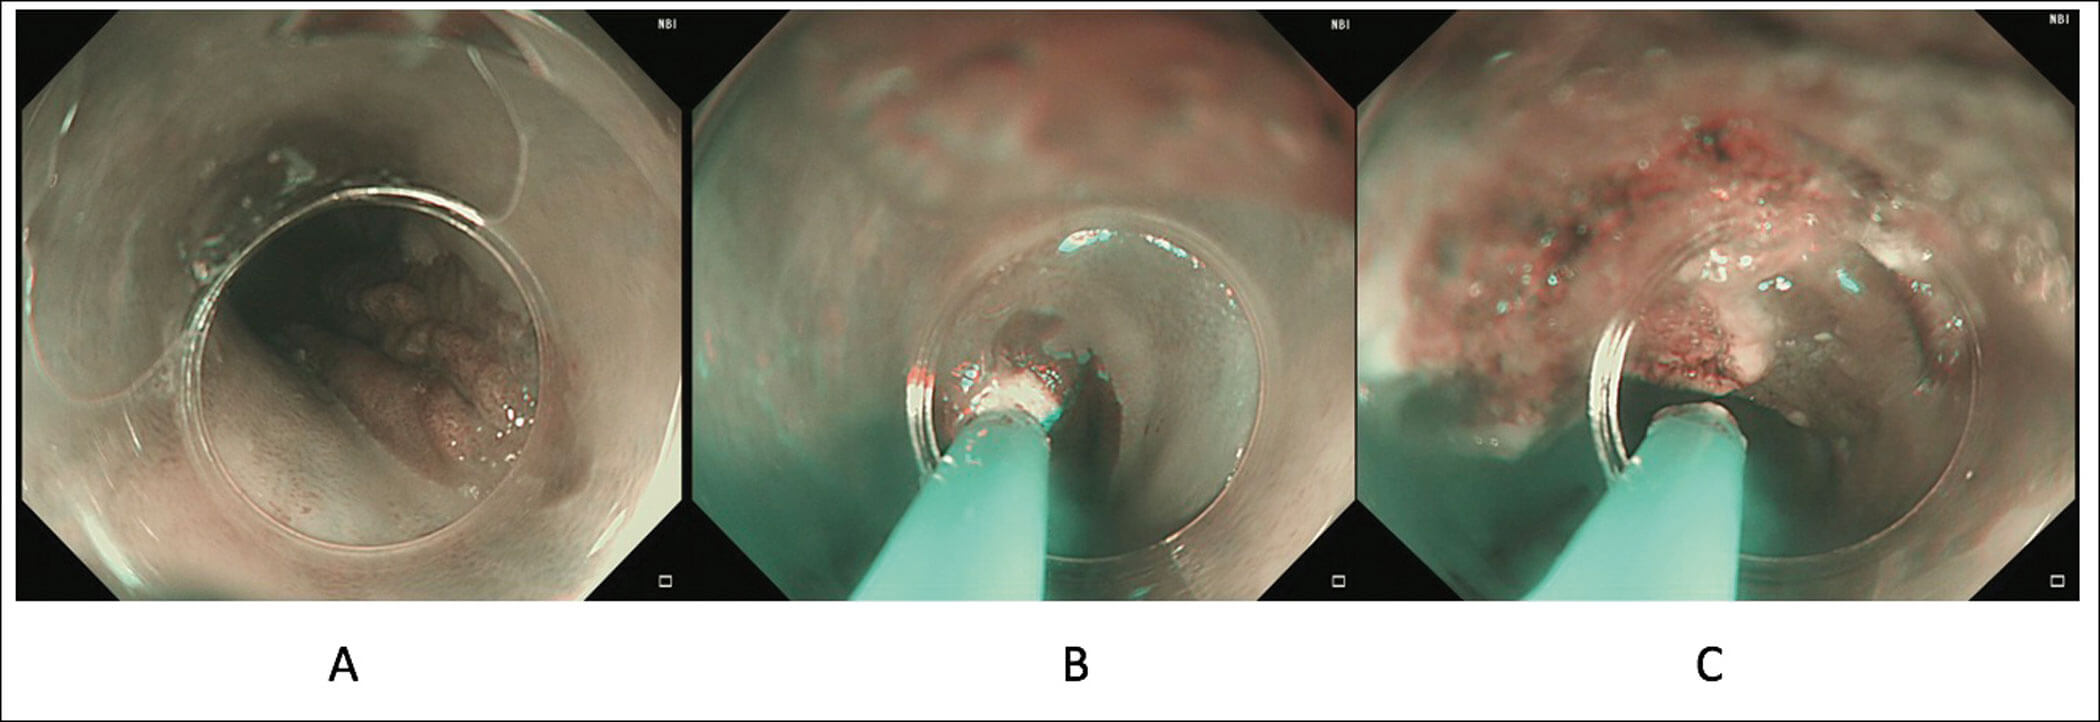

Figure 2. Treatment of a patient with large symptomatic gastric inlet patch (A) using APC where a cap

is used to provide stability in the proximal oesophagus and allow for targeted treatment (B and C).

This has been shown to be an effective modality for a GIP. Using a cap is useful to provide stabilisation in the proximal oesophagus (Figure 2). A prospective randomised sham-controlled trial showed a significant improvement in symptoms in the APC arm. Long-term efficacy after a median follow-up of 17 months was shown in 76% of patients [4].